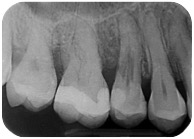

Sì, perchè ora faccio il figo, ma nel non lontano 2011, mi arriva una paziente con questo dente.

E questa è stata la mia reazione.

Cosa caspita era capitato a questo dente? Allarmato faccio vedere la radiografia a Federico, il mio socio, e anche lui pensa a qualcosa di brutto. Che so, un tumore di quelli incomprensibili che avevamo studiato solo sui libri di radiologia che si era insinuato all’interno di questo 4.6! ???

Quando nel 2013 mi è arrivato all’attenzione questo caso

Ho riconosciuto lo stesso fenomeno visto nella ragazza infestata da tessuti alieni di cui sopra e mi sono ricordato che all’università si era parlato di riassorbimenti esterni.